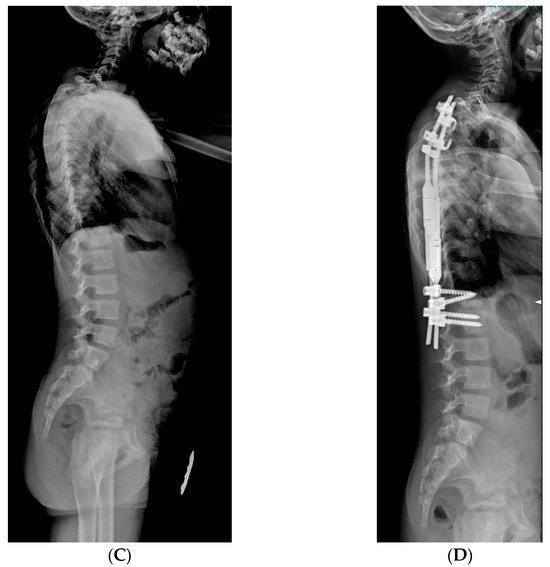

2.3.3. VEPTR: Vertical Expandable Prosthetic Titanium Rib